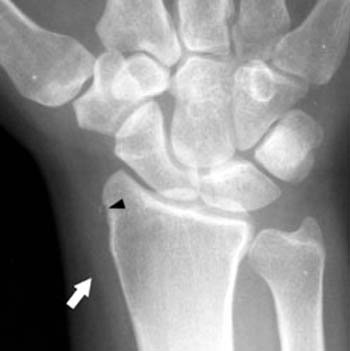

- Rtg nadgarstka – aby wykluczyć inne przyczyny bólu i obrzęku.